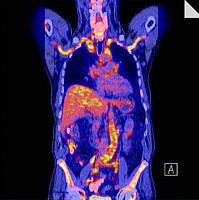

Die weltweit bisher größte Untersuchung zur Verbesserung der Diagnostik von unklarem Fieber führten jetzt Studienteams der Medizinischen Klinik 3 und der Nuklearmedizinischen Klinik durch. Dafür erhielten Patienten mit erhöhten Temperaturen und Entzündungen unklarer Herkunft bereits frühzeitig einen Ganzkörperscan mithilfe der Positronen-Emissionstomografie/Computertomografie (PET-CT), die zusätzlich zu den Standarduntersuchungen durchgeführt wurde.

Diese Technik ermöglicht die Darstellung krankhafter Stoffwechselvorgänge im Körper, zusätzlich zur genauen Analyse der Gewebestruktur. So können wir versteckte Entzündungen, Infektionen oder auch Tumoren sichtbar machen.